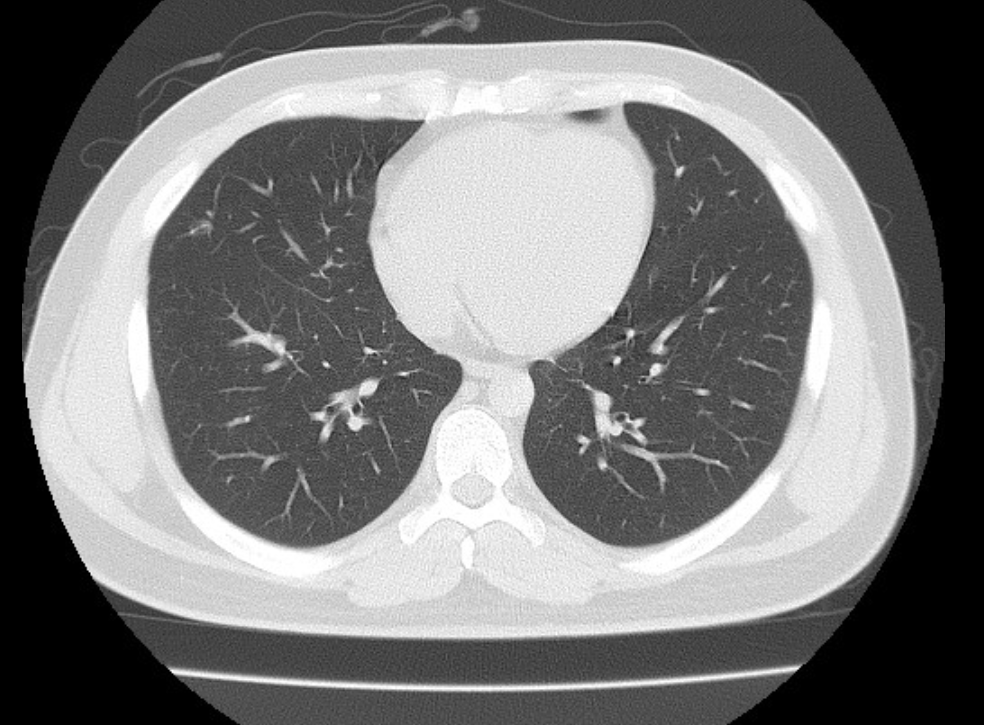

폐ct사진 받았는데 엄청 많더라구요.. 우중엽(40#)에 부분고형결절(6mm, 고형 2mm)결절이 있다고 소견을 받았는데 아래 ct사진 상 위험한 결절로 보이는지 판독좀 부탁드리겠습니다 ㅜㅜ. 다른 사진들 더 많지만 앞뒤 전후로 몇장씩만 가져왔어요..

• 2번 째 사진

밑에서 3번째 사진 우중엽 (보이기로는 왼쪽에 있는게 오른쪽 폐입니다)

흐릿하게 보이는 병변이네요

일반적으로 간유리음영과 결절이 같이 있을때 6mm 이상이면 암일확률이 1~2% 된다고 합니다. 저같으면 6개월후 추적검사를 해볼거 같네요